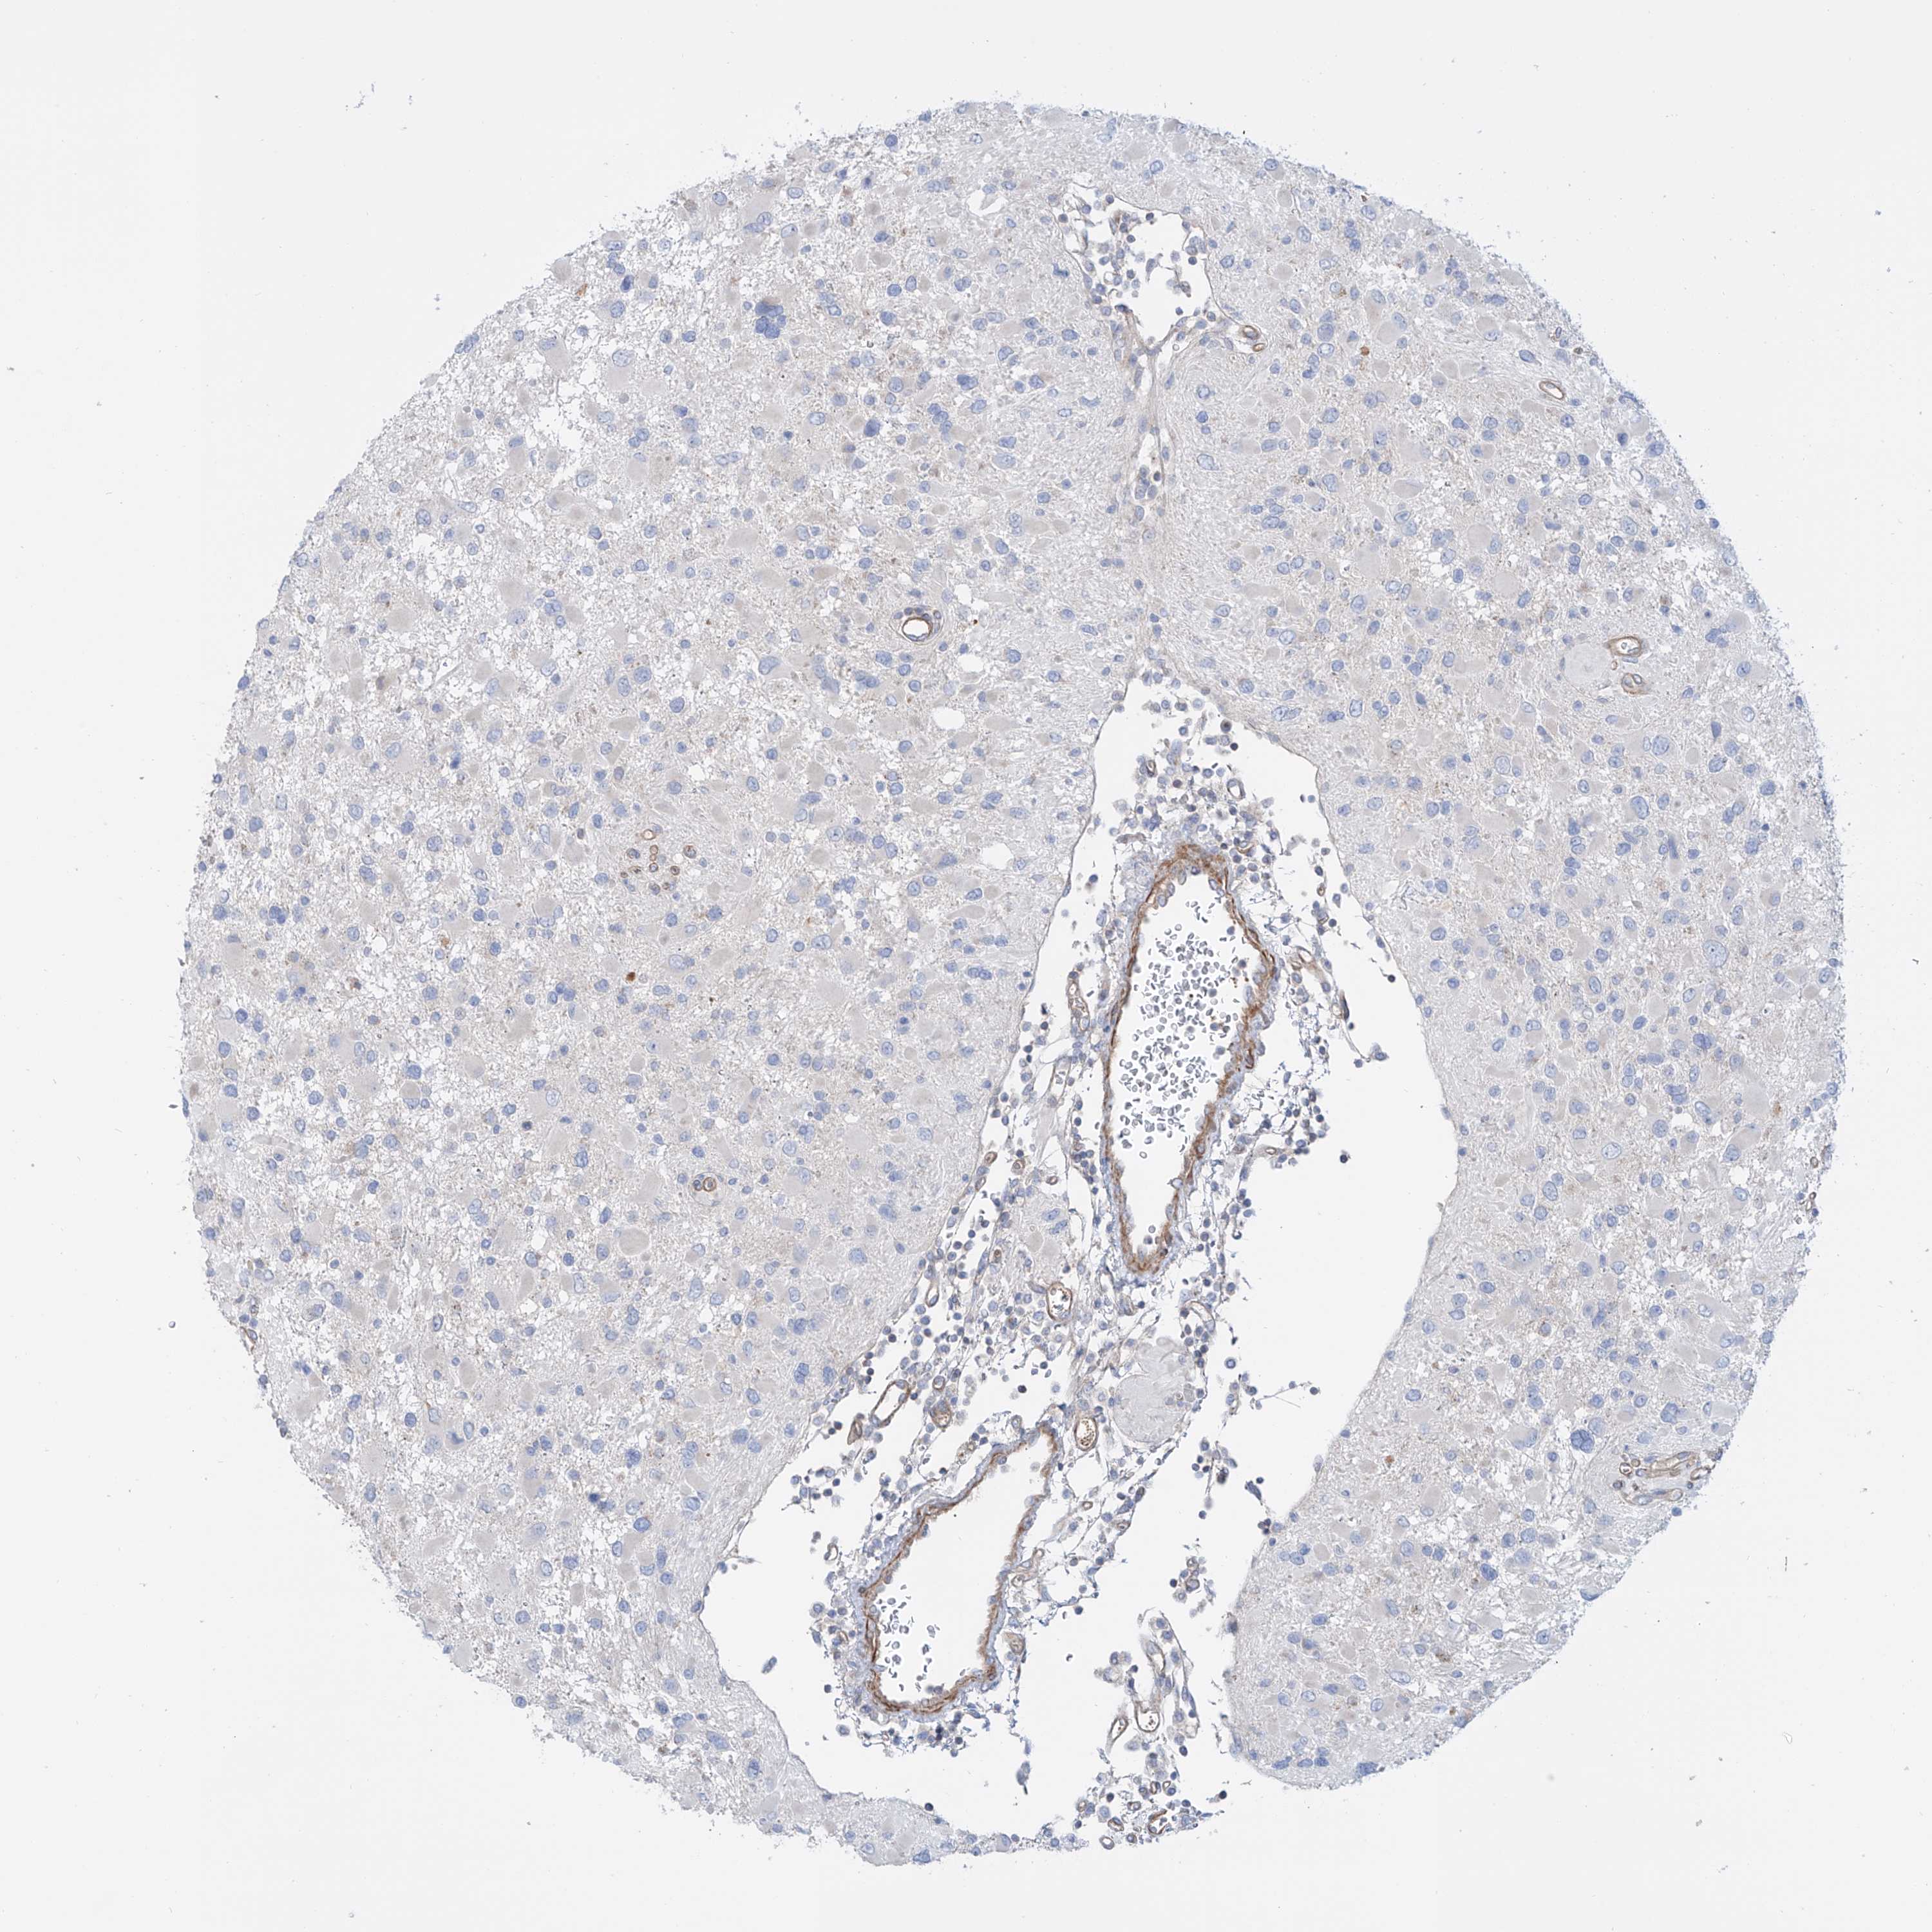

GLIOMA - Protein expressioni

A mouse-over function shows sample information and annotation data. Click on an image to view it in a full screen mode. Samples can be filtered based on level of antibody staining by selecting one or several of the following categories: high, medium, low and not detected. The assay and annotation is described here.

Note that samples used for immunohistochemistry by the Human Protein Atlas do not correspond to samples in the TCGA dataset.

Antibody stainingi

Antibody staining in the annotated cell types in the current human tissue is reported as not detected, low, medium, or high, based on conventional immunohistochemistry profiling in selected tissues. This score is based on the combination of the staining intensity and fraction of stained cells.

Each image is clickable and will lead to virtual microscopy that enables deeper exploration of all samples and also displays staining intensity scores, fraction scores and subcellular localization as well as patient and tissue information for each sample.

Antibody HPA031678

Staining

High

Medium

Low

Not detected

Intensity

Strong

Moderate

Weak

Negative

Quantity

>75%

75%-25%

<25%

None

Location

Nuclear

Cytoplasmic/membranous

Cytoplasmic/membranous,nuclear

Glioma, malignant, High grade

Glioma, malignant, Low grade

Glioblastoma, NOS